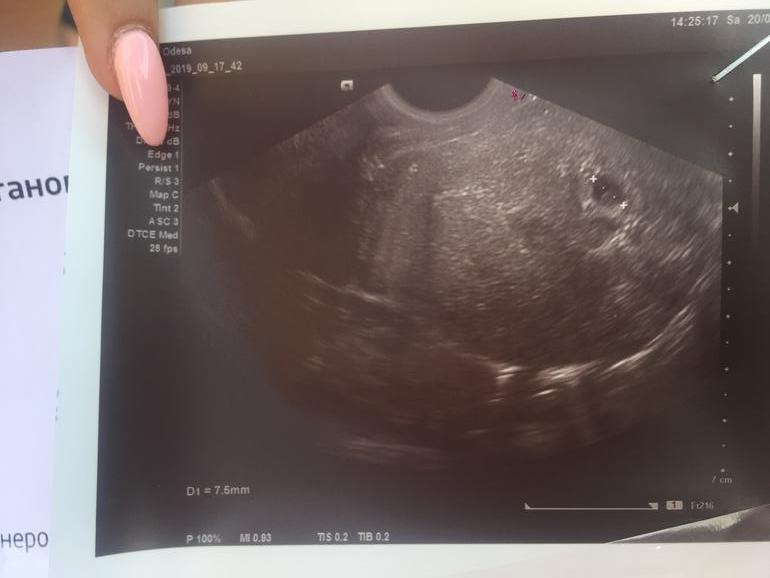

Девчонки , была на узи 20.07.19р; пошла в другую поликлинику (тоже в частную) они по выходным принимают мне удобно! Врачиха твёрдо поздравила, у меня аж отлегло! Моя кроха 7,5 мм! Та и хгч уже вырос 2499мме/мл!через пару недель пойду послушаю сердечко(ато рано ещё)